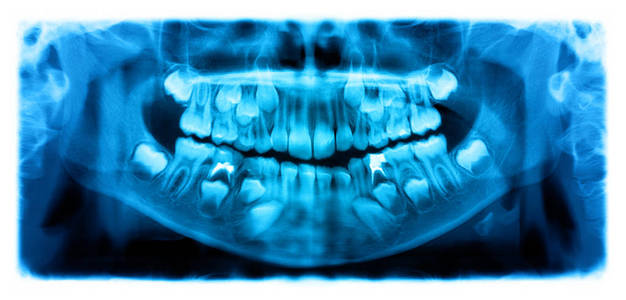

分段下颌骨的全景牙科 X 射线

该数据集由 116 名患者的匿名且去识别化的全景牙科 X 射线扫描图像和分割掩模组成。主题涵盖广泛的牙科疾病,从健康到部分无牙颌和全口无牙颌病例。